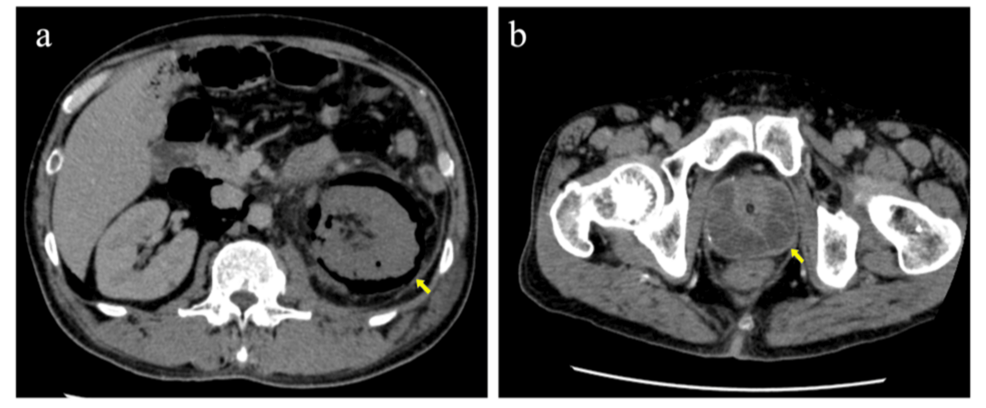

Un reciente caso clínico publicado en Cureus detalla una complicación grave de la pielonefritis enfisematosa causada por la bacteria Klebsiella pneumoniae. El informe describe a un paciente que desarrolló múltiples abscesos metastásicos y un paro respiratorio transitorio como resultado de la infección.

El caso reportado por Cureus ilustra la capacidad de la infección por Klebsiella pneumoniae para manifestarse de manera inusual, incluso imitando lesiones metastásicas, lo que puede complicar el diagnóstico inicial.